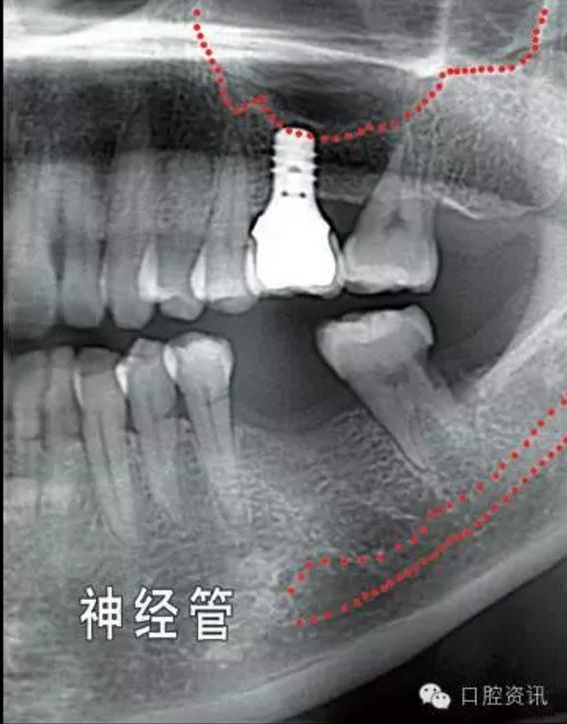

就種植手術(shù)本身而言,您頜面部一些重要結(jié)構(gòu)(例如下頜神經(jīng),上頜

竇) 的位置和形態(tài)會增加手術(shù)風險和操作難度,為避免因手術(shù)損傷這

些重要結(jié)構(gòu),我們要求您手術(shù)前拍攝X光片作為參考,以便牙醫(yī)結(jié)合這些材料和您具體分析手術(shù)的風險程度。

10.jpg

圖10. 可能影響種植牙手術(shù)操作的解剖結(jié)構(gòu)